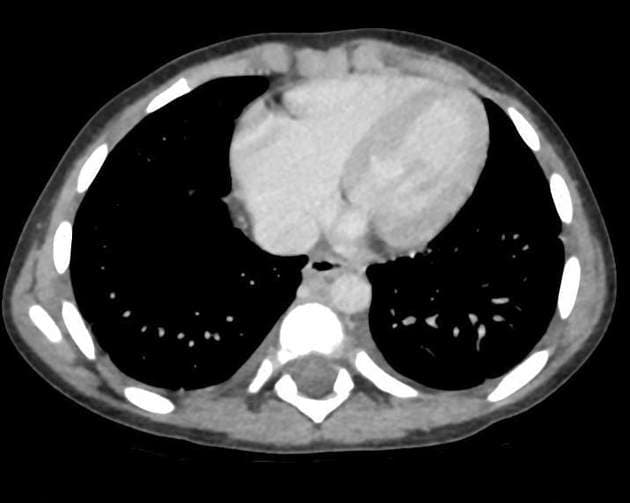

Đau đầu mới xuất hiện và liệt nửa người trái ở bệnh nhân đang điều trị ung thư phổi tế bào không nhỏ.

Phát hiện nhiều nốt (nodule) và khối (mass) ở vùng trên lều, trong đó tổn thương lớn nhất nằm ở thùy chẩm phải, kích thước khoảng 34 x 29 x 30 mm.

Các tổn thương ở nhu mô não (brain parenchyma), sọ vòm (calvarium) và màng não (meninges) vùng trán trái phù hợp với di căn nội sọ (intracranial metastases).

Di căn nội sọ (intracranial metastases)